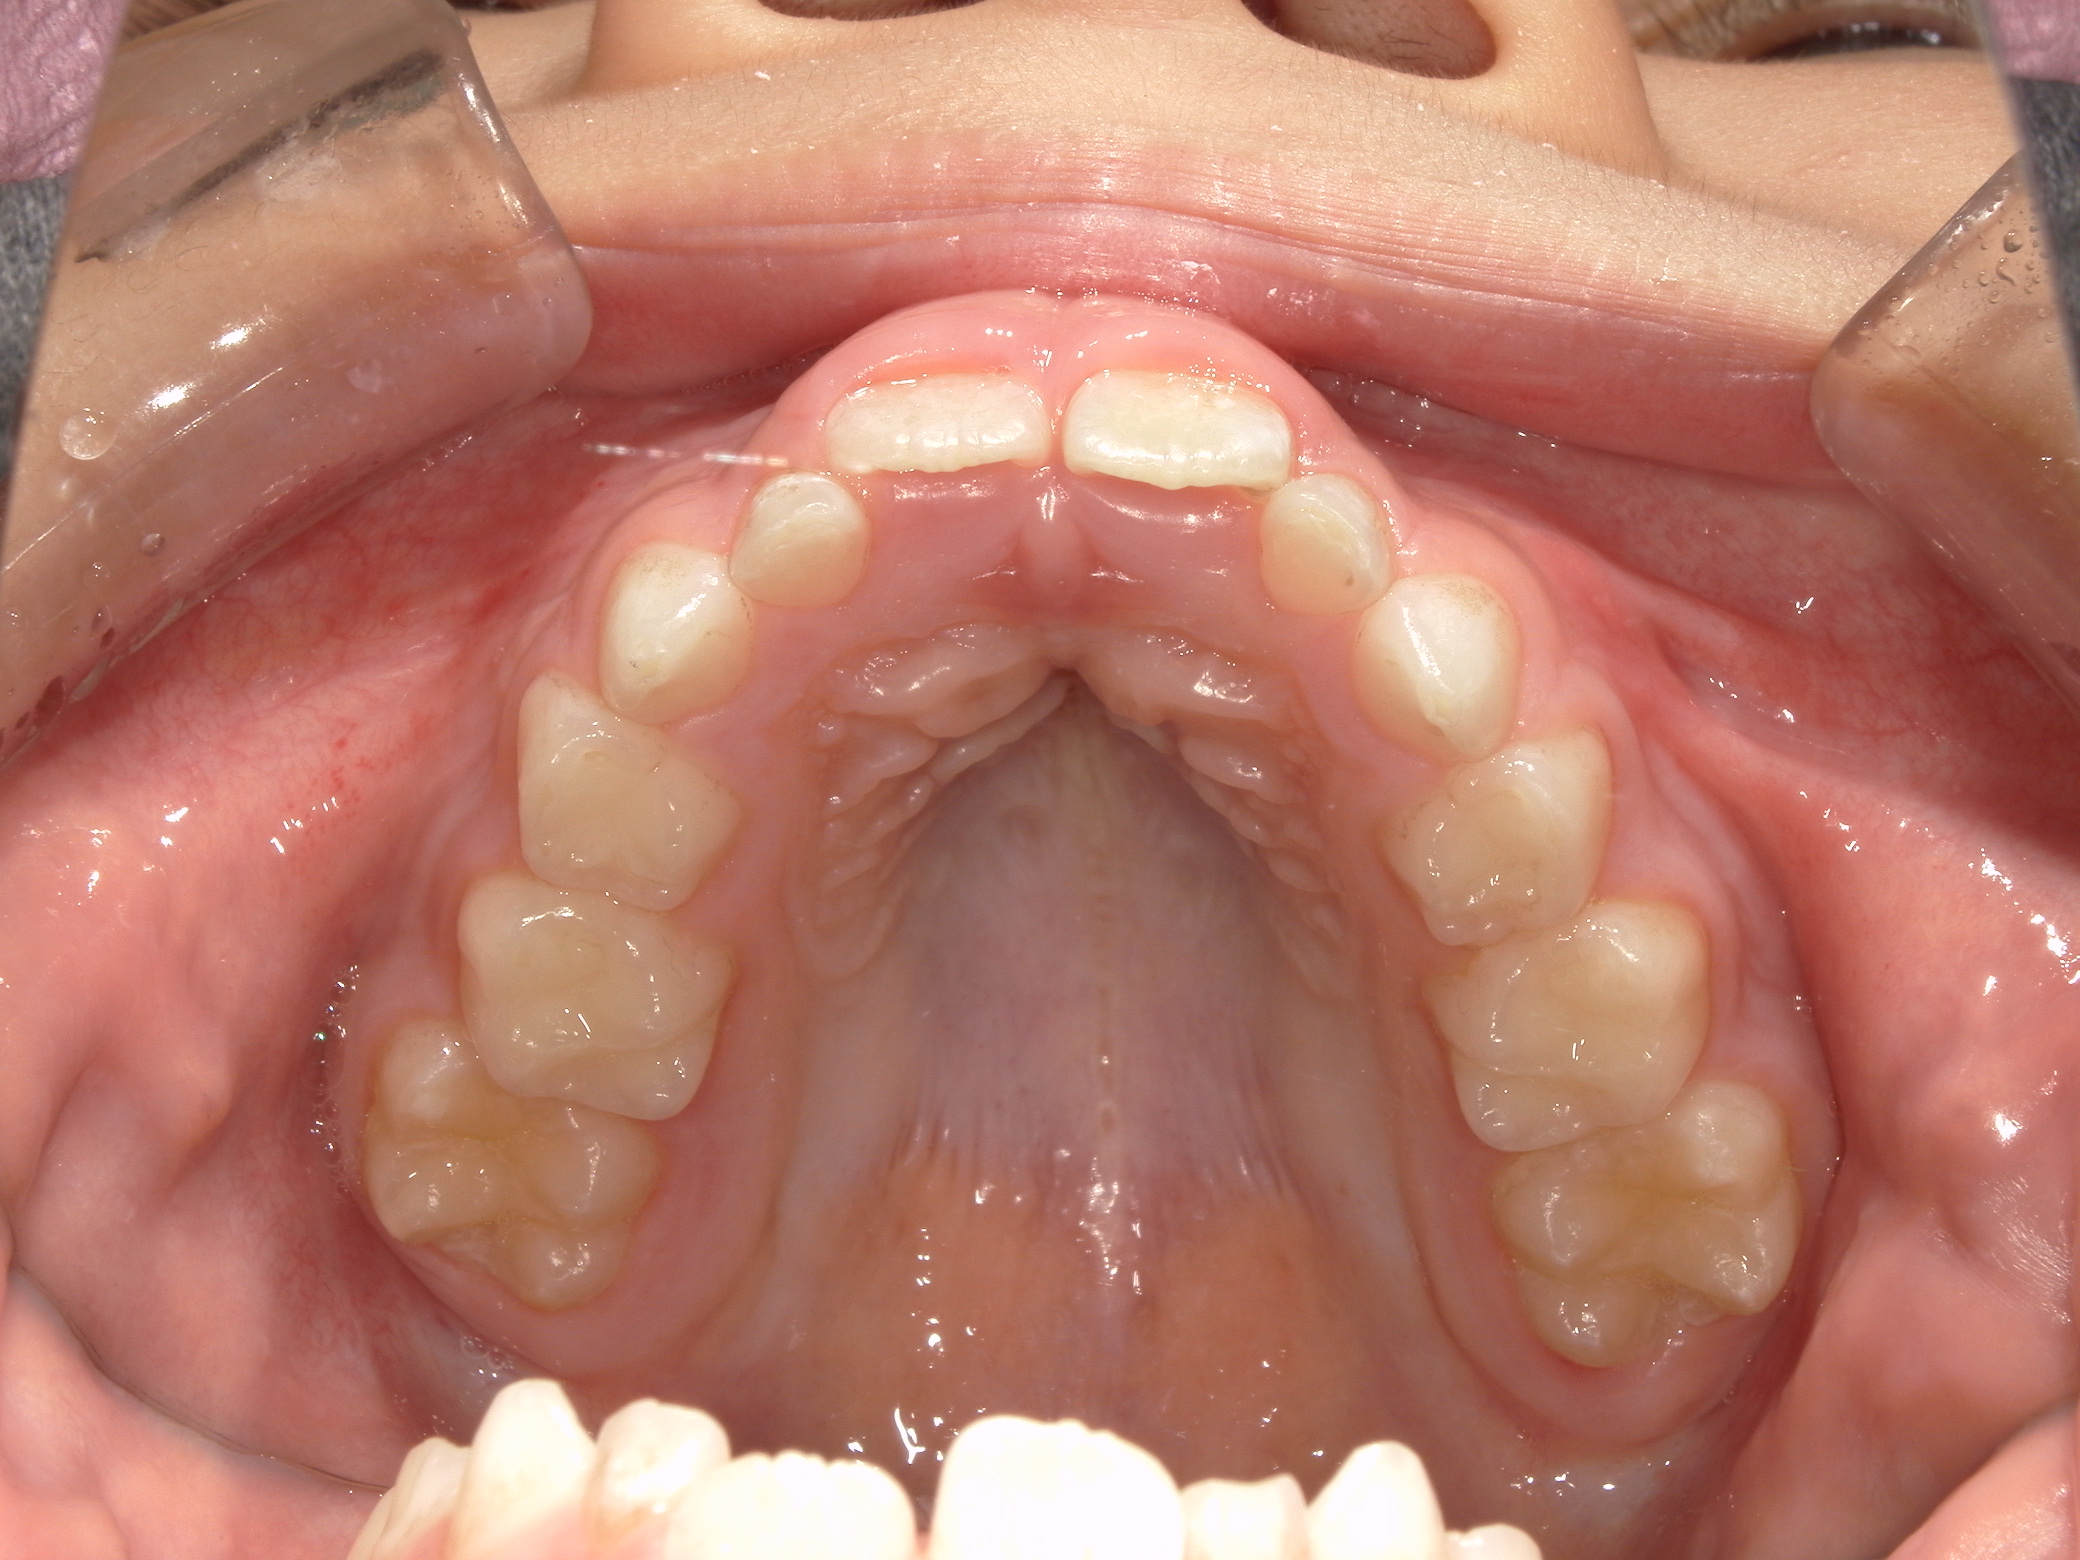

受け口(上顎歯列弓狭窄による臼歯部交叉咬合)

6歳 男性

上顎歯列拡大による交叉咬合の改善

急速拡大装置

495,000円(税込)

約1年半

上顎がかなり狭窄した状態でした。固定式拡大装置で歯列および顎骨を拡大し、奥歯のかみ合わせも改善しています。

中学生以降になると骨が固くなりこのようにキレイには拡大できないため早期治療が功を奏した例です。

2期治療のための精密検査が必要です。

リスク:歯肉退縮、歯根吸収、後戻り、予期せぬ成長